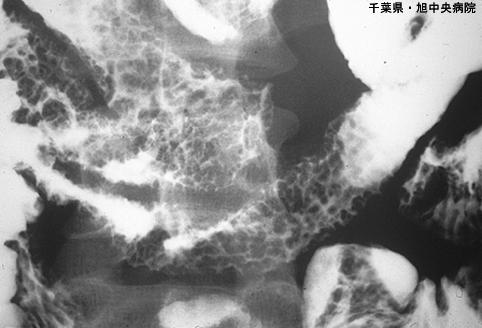

Amiloidosis del Intestino Delgado acompañada de ulceración y mucosa rugosa de tipo erosiva (Caso presentado por Hospital Central de Asahi, Prefectura de Chiba)

Enfermedad Inflamatoria - Ulcerativa/Amiloidosis del Tubo Digestivo

intestino delgado/mas de dos

Rayos X